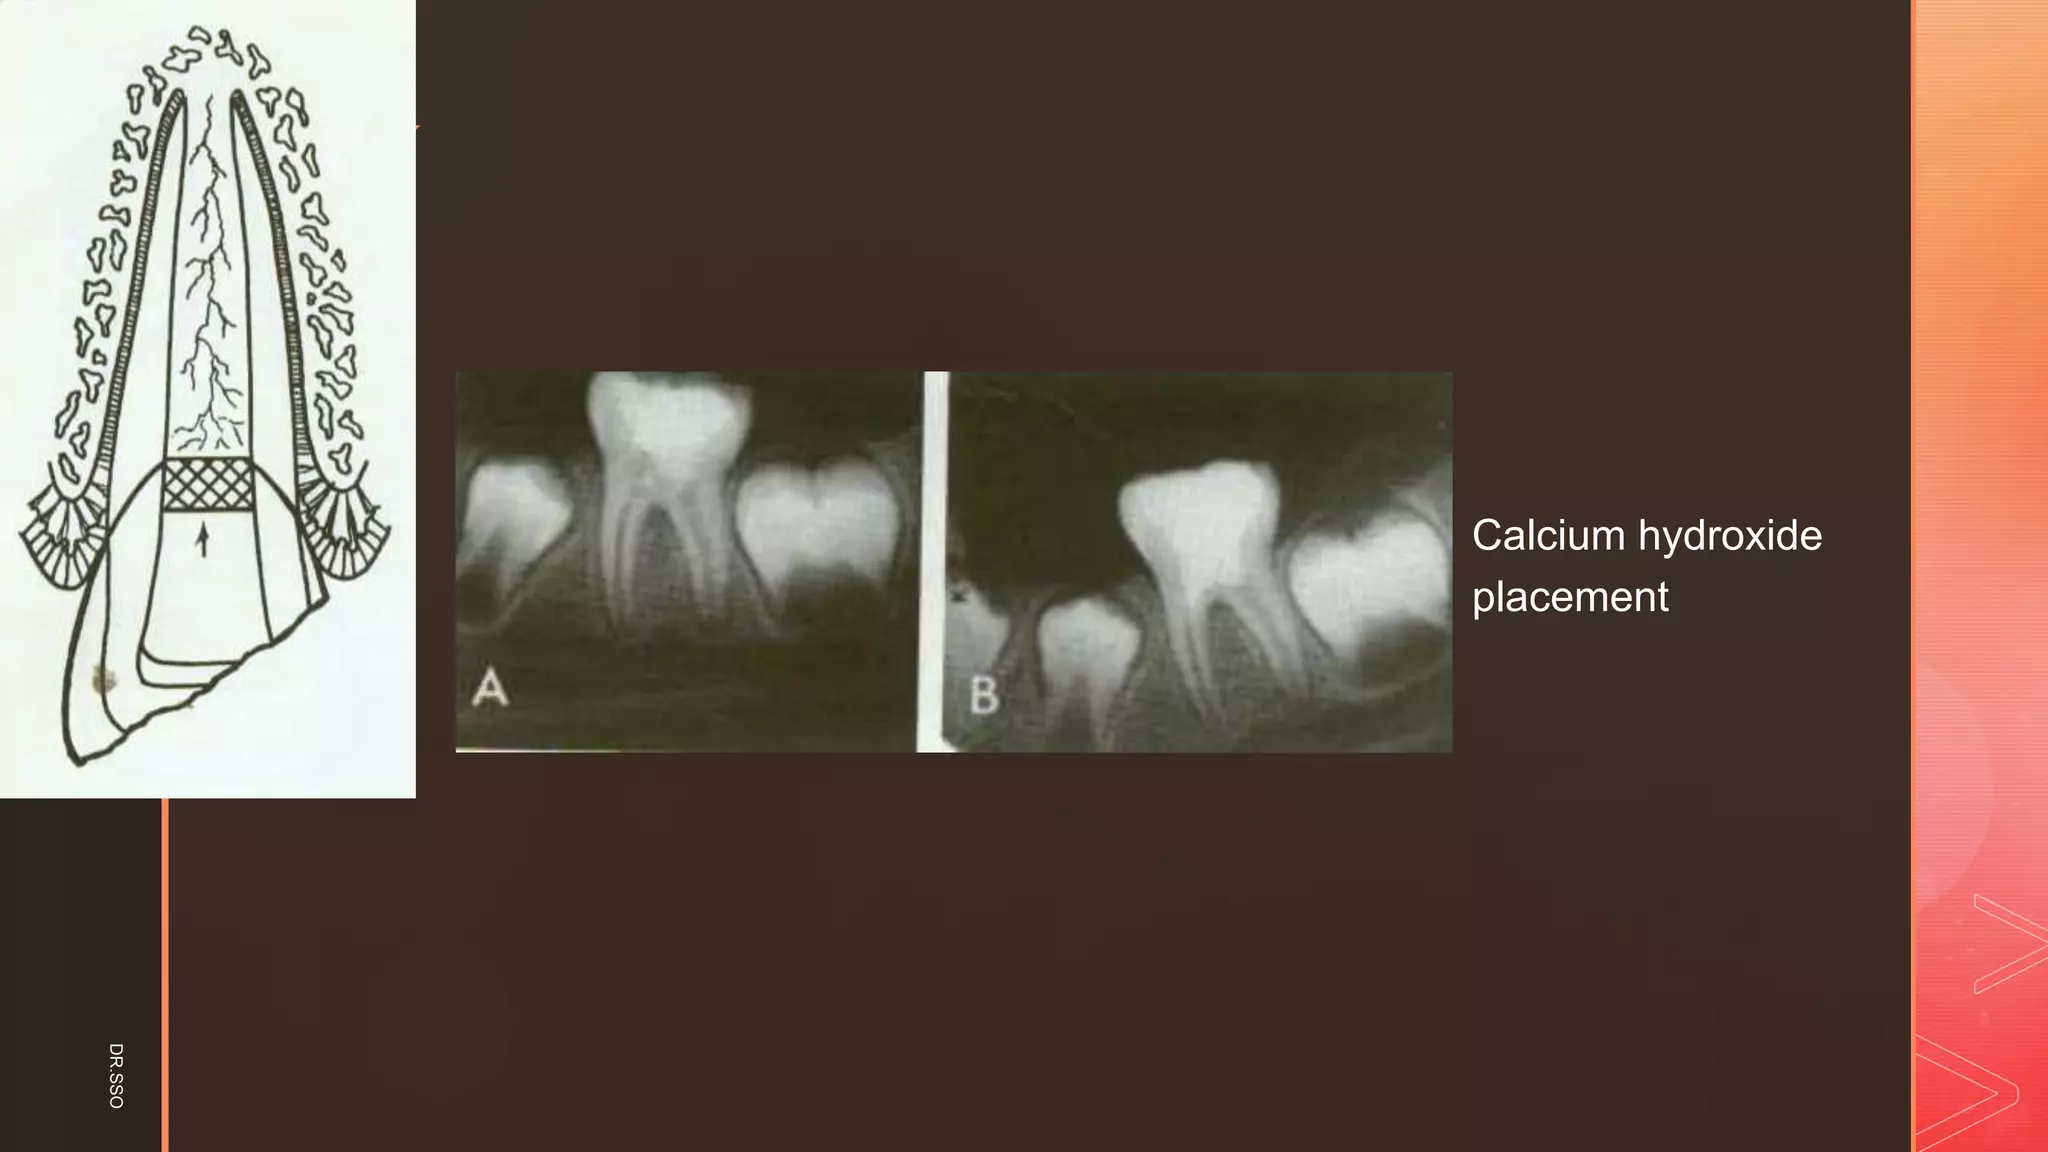

▪ [Ca(OH)2]: Calcium hydroxide powder was

mixed with saline to a thick consistency. The

paste was carefully placed on the pulp stump

surface 1 to 2 mm thick.

▪ Calcium hydroxide

placement